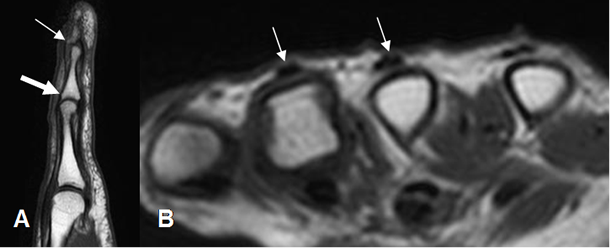

Con la RM se aprecian como imágenes hipointensas en todas las secuencias y mejor evaluados en vistas axial y sagital. (Fig 29, 30 y 31).

Fig 29. Mecanismo extensor normal.

A: RM sagital en T1. Inserción de mecanismo extensor en la base de la falange media (Flecha gruesa) y en la base de la falange distal (Flecha delgada).

B: RM axial en T1. Mecanismo extensor normal, en el dorso de los metacarpianos.

Fig 30. Mecanismo flexor normal.

A: RM sagital en T1. Inserción del flexor superficial en la base de la falange media (Flecha gruesa) y del flexor profundo, en la base de la falange distal (Flecha delgada).

B: RM axial en T2. Mecanismo flexor, fijado por las poleas en las falanges.